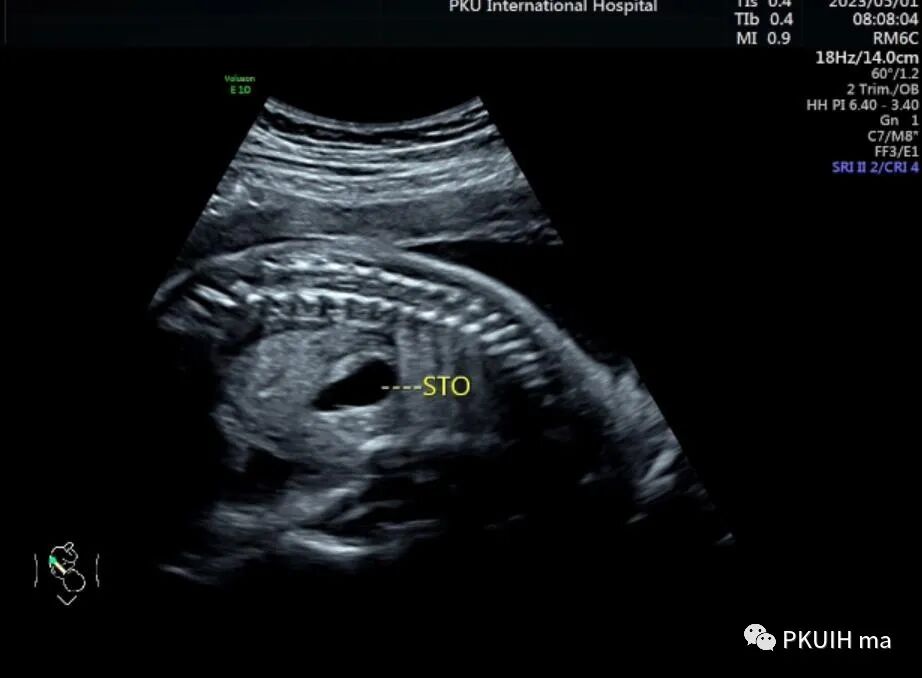

今天跟大家分享一例镜面人的超声图像。患者22周常规系统排畸未提示异常,本次24周+行胎儿心脏超声检查发现内脏反位。图像如下

胎儿头位(右枕横位),胎儿小脑半球和脊柱均在右侧,采用右手法则判断近场为胎儿的左侧远场胎儿的右侧

胎儿胃泡位于右侧,肝脏和胆囊位于左侧,主动脉位于脊柱右前方,下腔静脉位于脊柱左前方